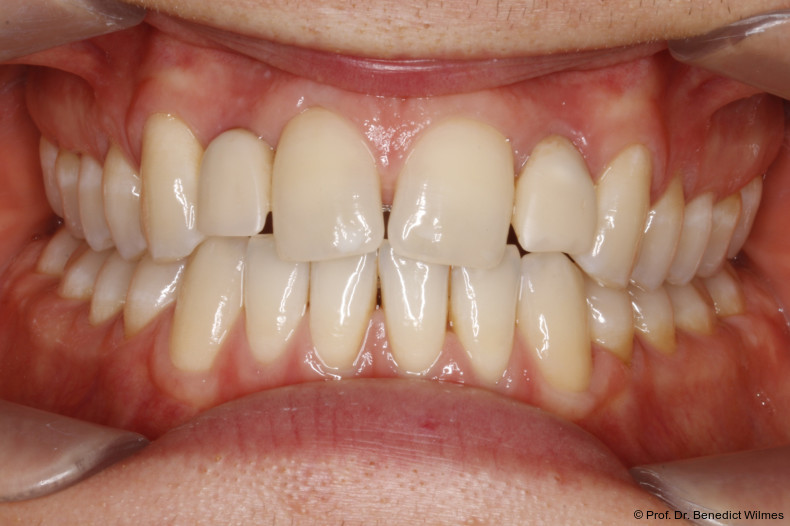

Ein 14-jähriger Patient wurde bei Aplasie der beiden oberen seitlichen Schneidezähne mit dem Ziel der beidseitigen Lückenöffnung kieferorthopädisch therapiert (Abb. 1a+b). Zum Ende der kieferorthopädischen Behandlung wurden zwei Miniimplantate in Regio 2er als temporärer Zahnersatz inseriert (Benefit System, PSM, 2 x 13 mm, Abb. 2a+b). Nach Abdrucknahme wurden Kronen auf den Peek-Abutments modelliert und diese mit Kunststoff auf die Abutments geklebt (Abb. 3a–d). In den Abbildungen 3 und 4 sind die klinischen und röntgenologischen Nachkontrollen innerhalb der nächsten achteinhalb Jahre dokumentiert. Man erkennt einen sowohl in der Höhe als auch in bukkopalatinalen Breite verbleibenden gesunden Knochen ohne Anzeichen einer Atrophie. Im Alter von 23 Jahren wurden die definitiven Implantate ohne die Notwendigkeit einer Augmentation eingesetzt (Abb. 5) und nach Einheilung prothetisch versorgt (Abb. 6a–e und Abb. 7a–c).

Bei einer elfjährigen Patientin fehlten bei Zustand nach Frontzahntrauma im Alter von neun Jahren beide oberen mittleren Schneidezähne (Abb. 8a+b). Als temporärer Ersatz wurden Miniimplantate (Abb. 9, 2 x 13 mm) eingesetzt und Kronen im Labor angefertigt, welche auf den Miniimplantaten verschraubt wurden (Abb. 10a+b). Die Miniimplantate wurden im Alter von 19 Jahren, also nach achtjähriger Nutzung (Abb. 11a+b), durch dentale Implantate ersetzt.